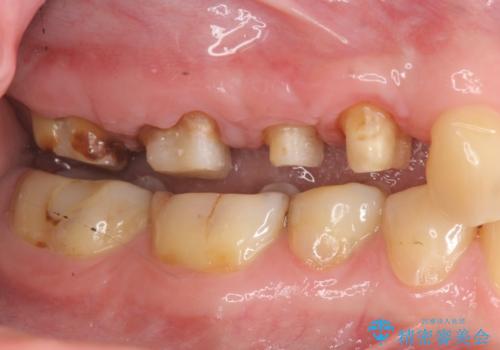

- 近医で「根尖の病変が大きく、残すことができない、歯を抜くしかない。」、と言われ歯を抜く以外の手段がないかを相談しに来院されました。

検査の結果、根管・クリアランス・虫歯といった複合的な問題が認められ、以下のような治療計画を進めることとしました。

根尖病変 →マイクロスコープを用いた精密根管治療の実施

クラウンの製作スペースの付属 →歯周外科によるスペースの確保

機能の回復・再感染の予防 →精密なジルコニアクラウンの作製